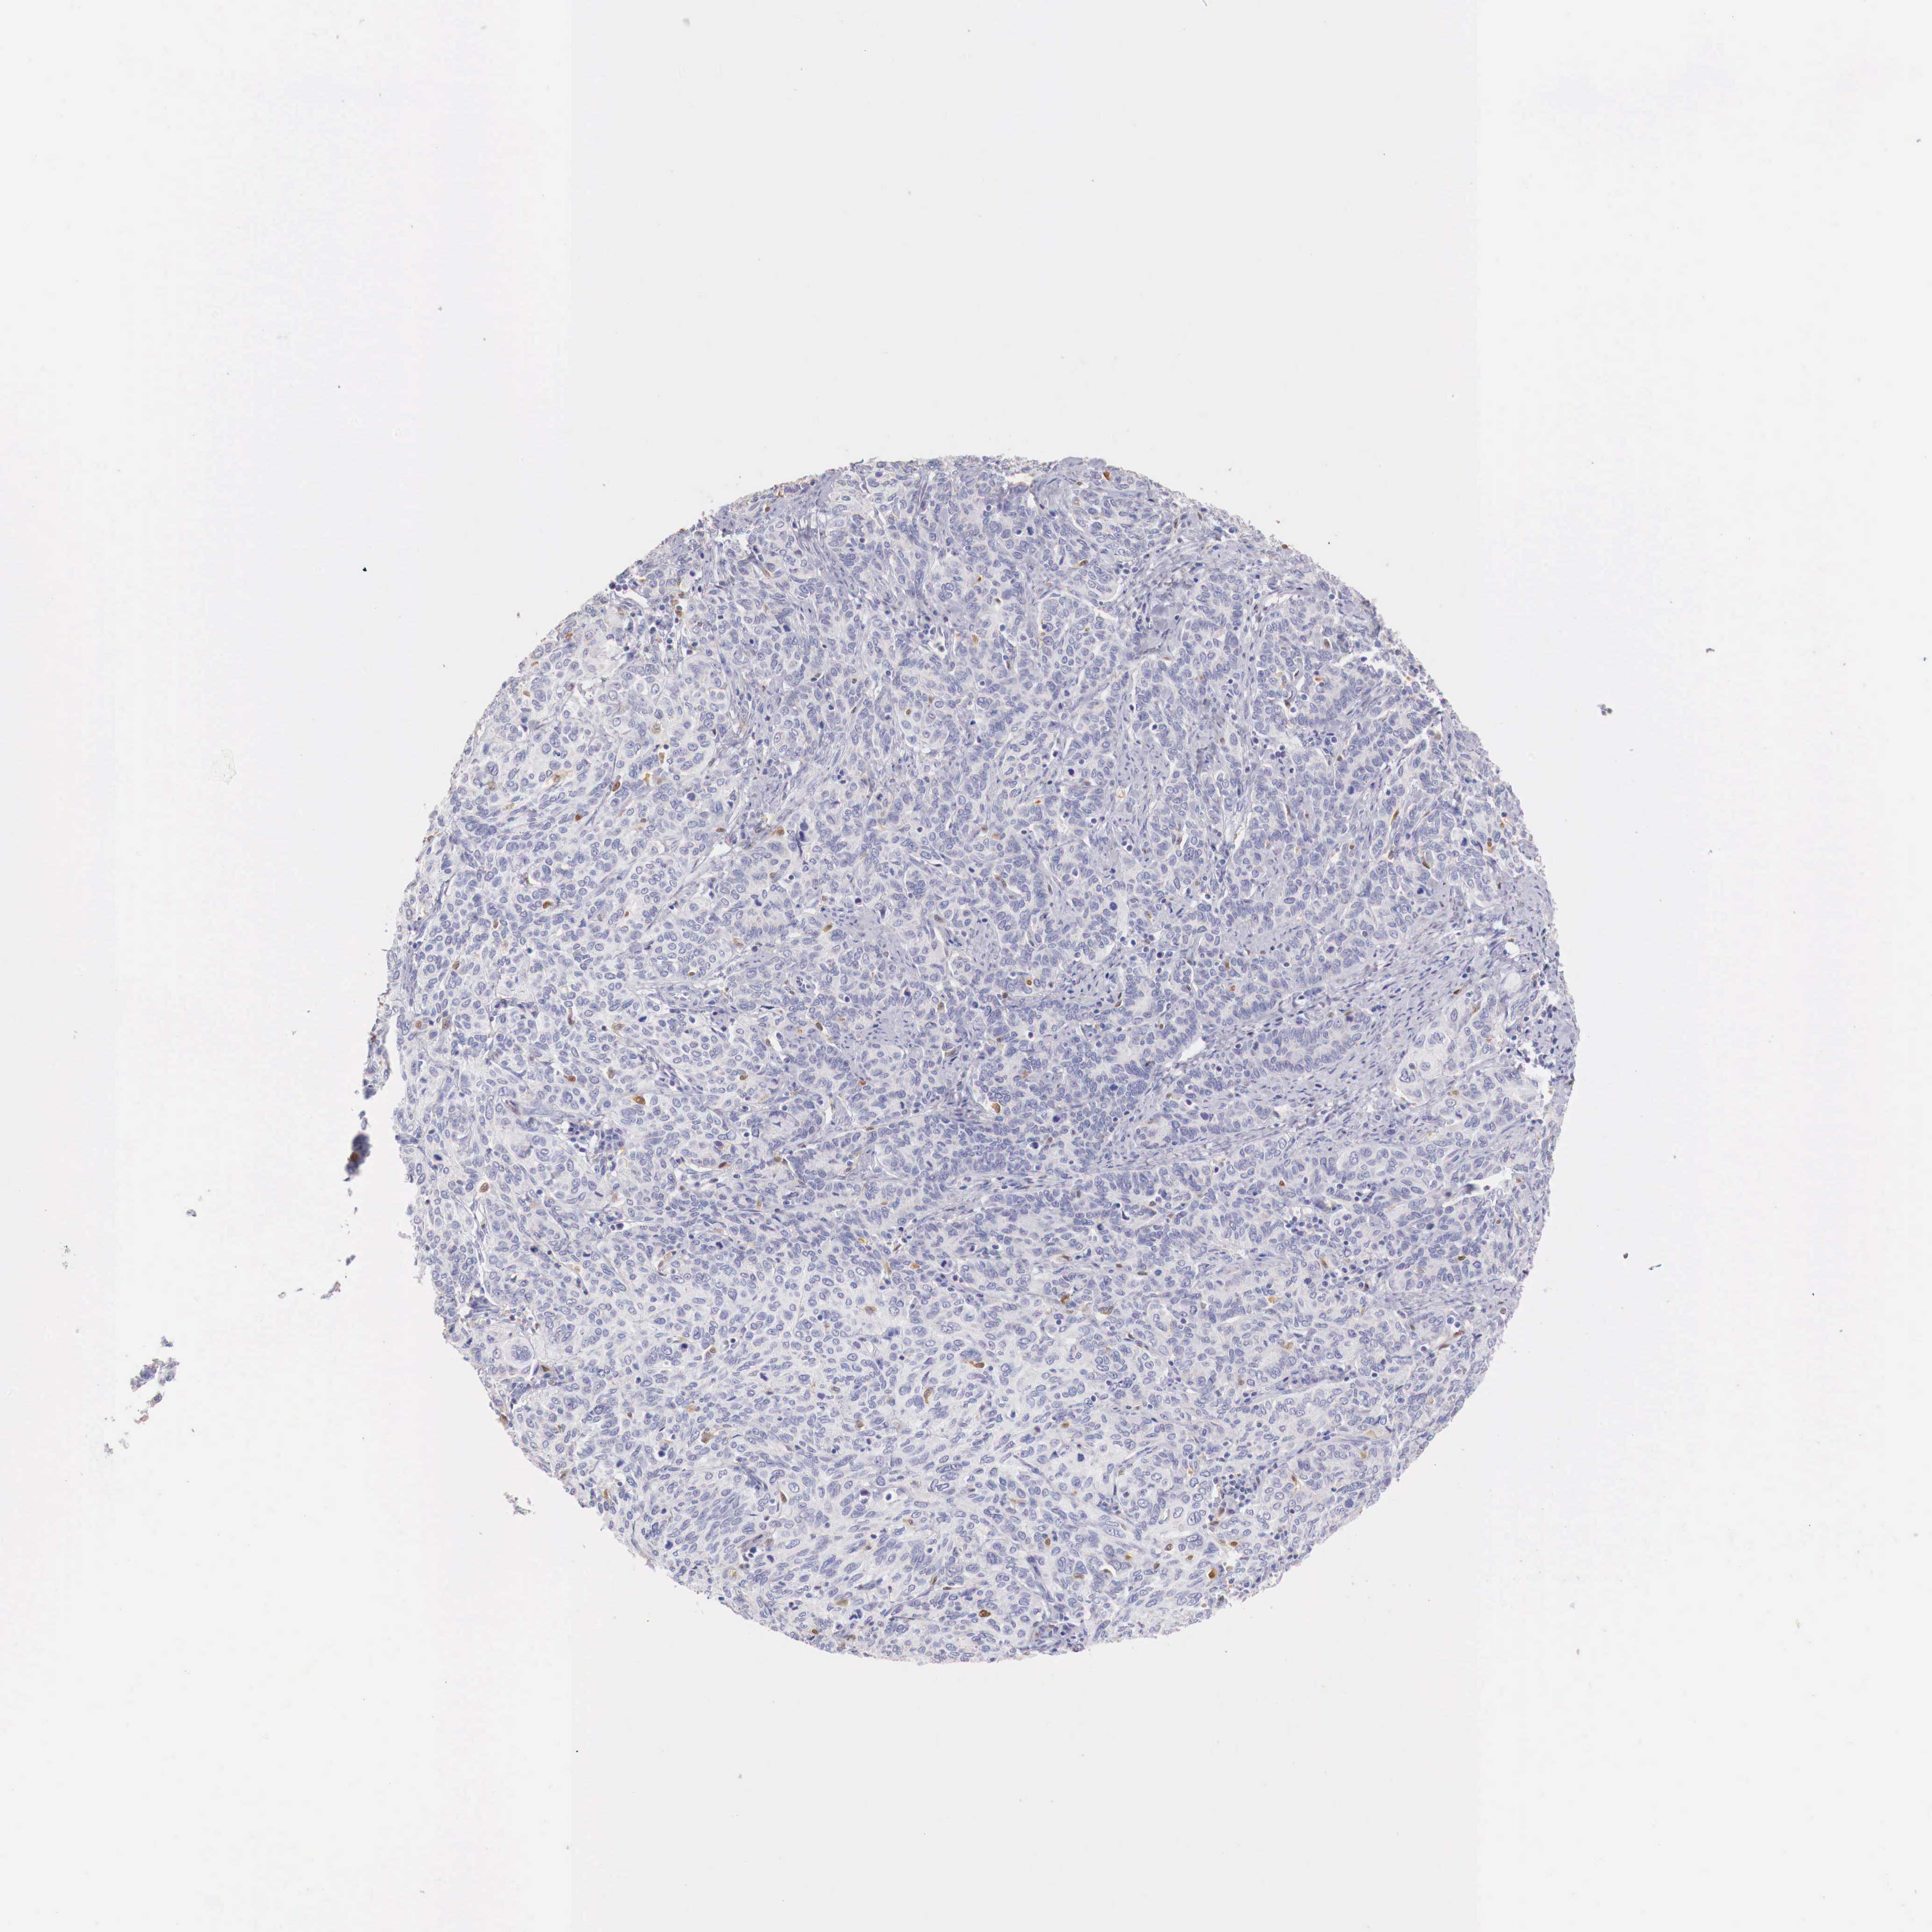

CERVICAL CANCER - Protein expressioni

A mouse-over function shows sample information and annotation data. Click on an image to view it in a full screen mode. Samples can be filtered based on level of antibody staining by selecting one or several of the following categories: high, medium, low and not detected. The assay and annotation is described here.

Note that samples used for immunohistochemistry by the Human Protein Atlas do not correspond to samples in the TCGA dataset.

Antibody stainingi

Antibody staining in the annotated cell types in the current human tissue is reported as not detected, low, medium, or high, based on conventional immunohistochemistry profiling in selected tissues. This score is based on the combination of the staining intensity and fraction of stained cells.

Each image is clickable and will lead to virtual microscopy that enables deeper exploration of all samples and also displays staining intensity scores, fraction scores and subcellular localization as well as patient and tissue information for each sample.

Antibody HPA000428

Antibody HPA000522

Staining

High

Medium

Low

Not detected

Intensity

Strong

Moderate

Weak

Negative

Quantity

>75%

75%-25%

<25%

None

Location

Nuclear

Cytoplasmic/membranous

Cytoplasmic/membranous,nuclear

Adenocarcinoma, NOS

Squamous cell carcinoma, NOS